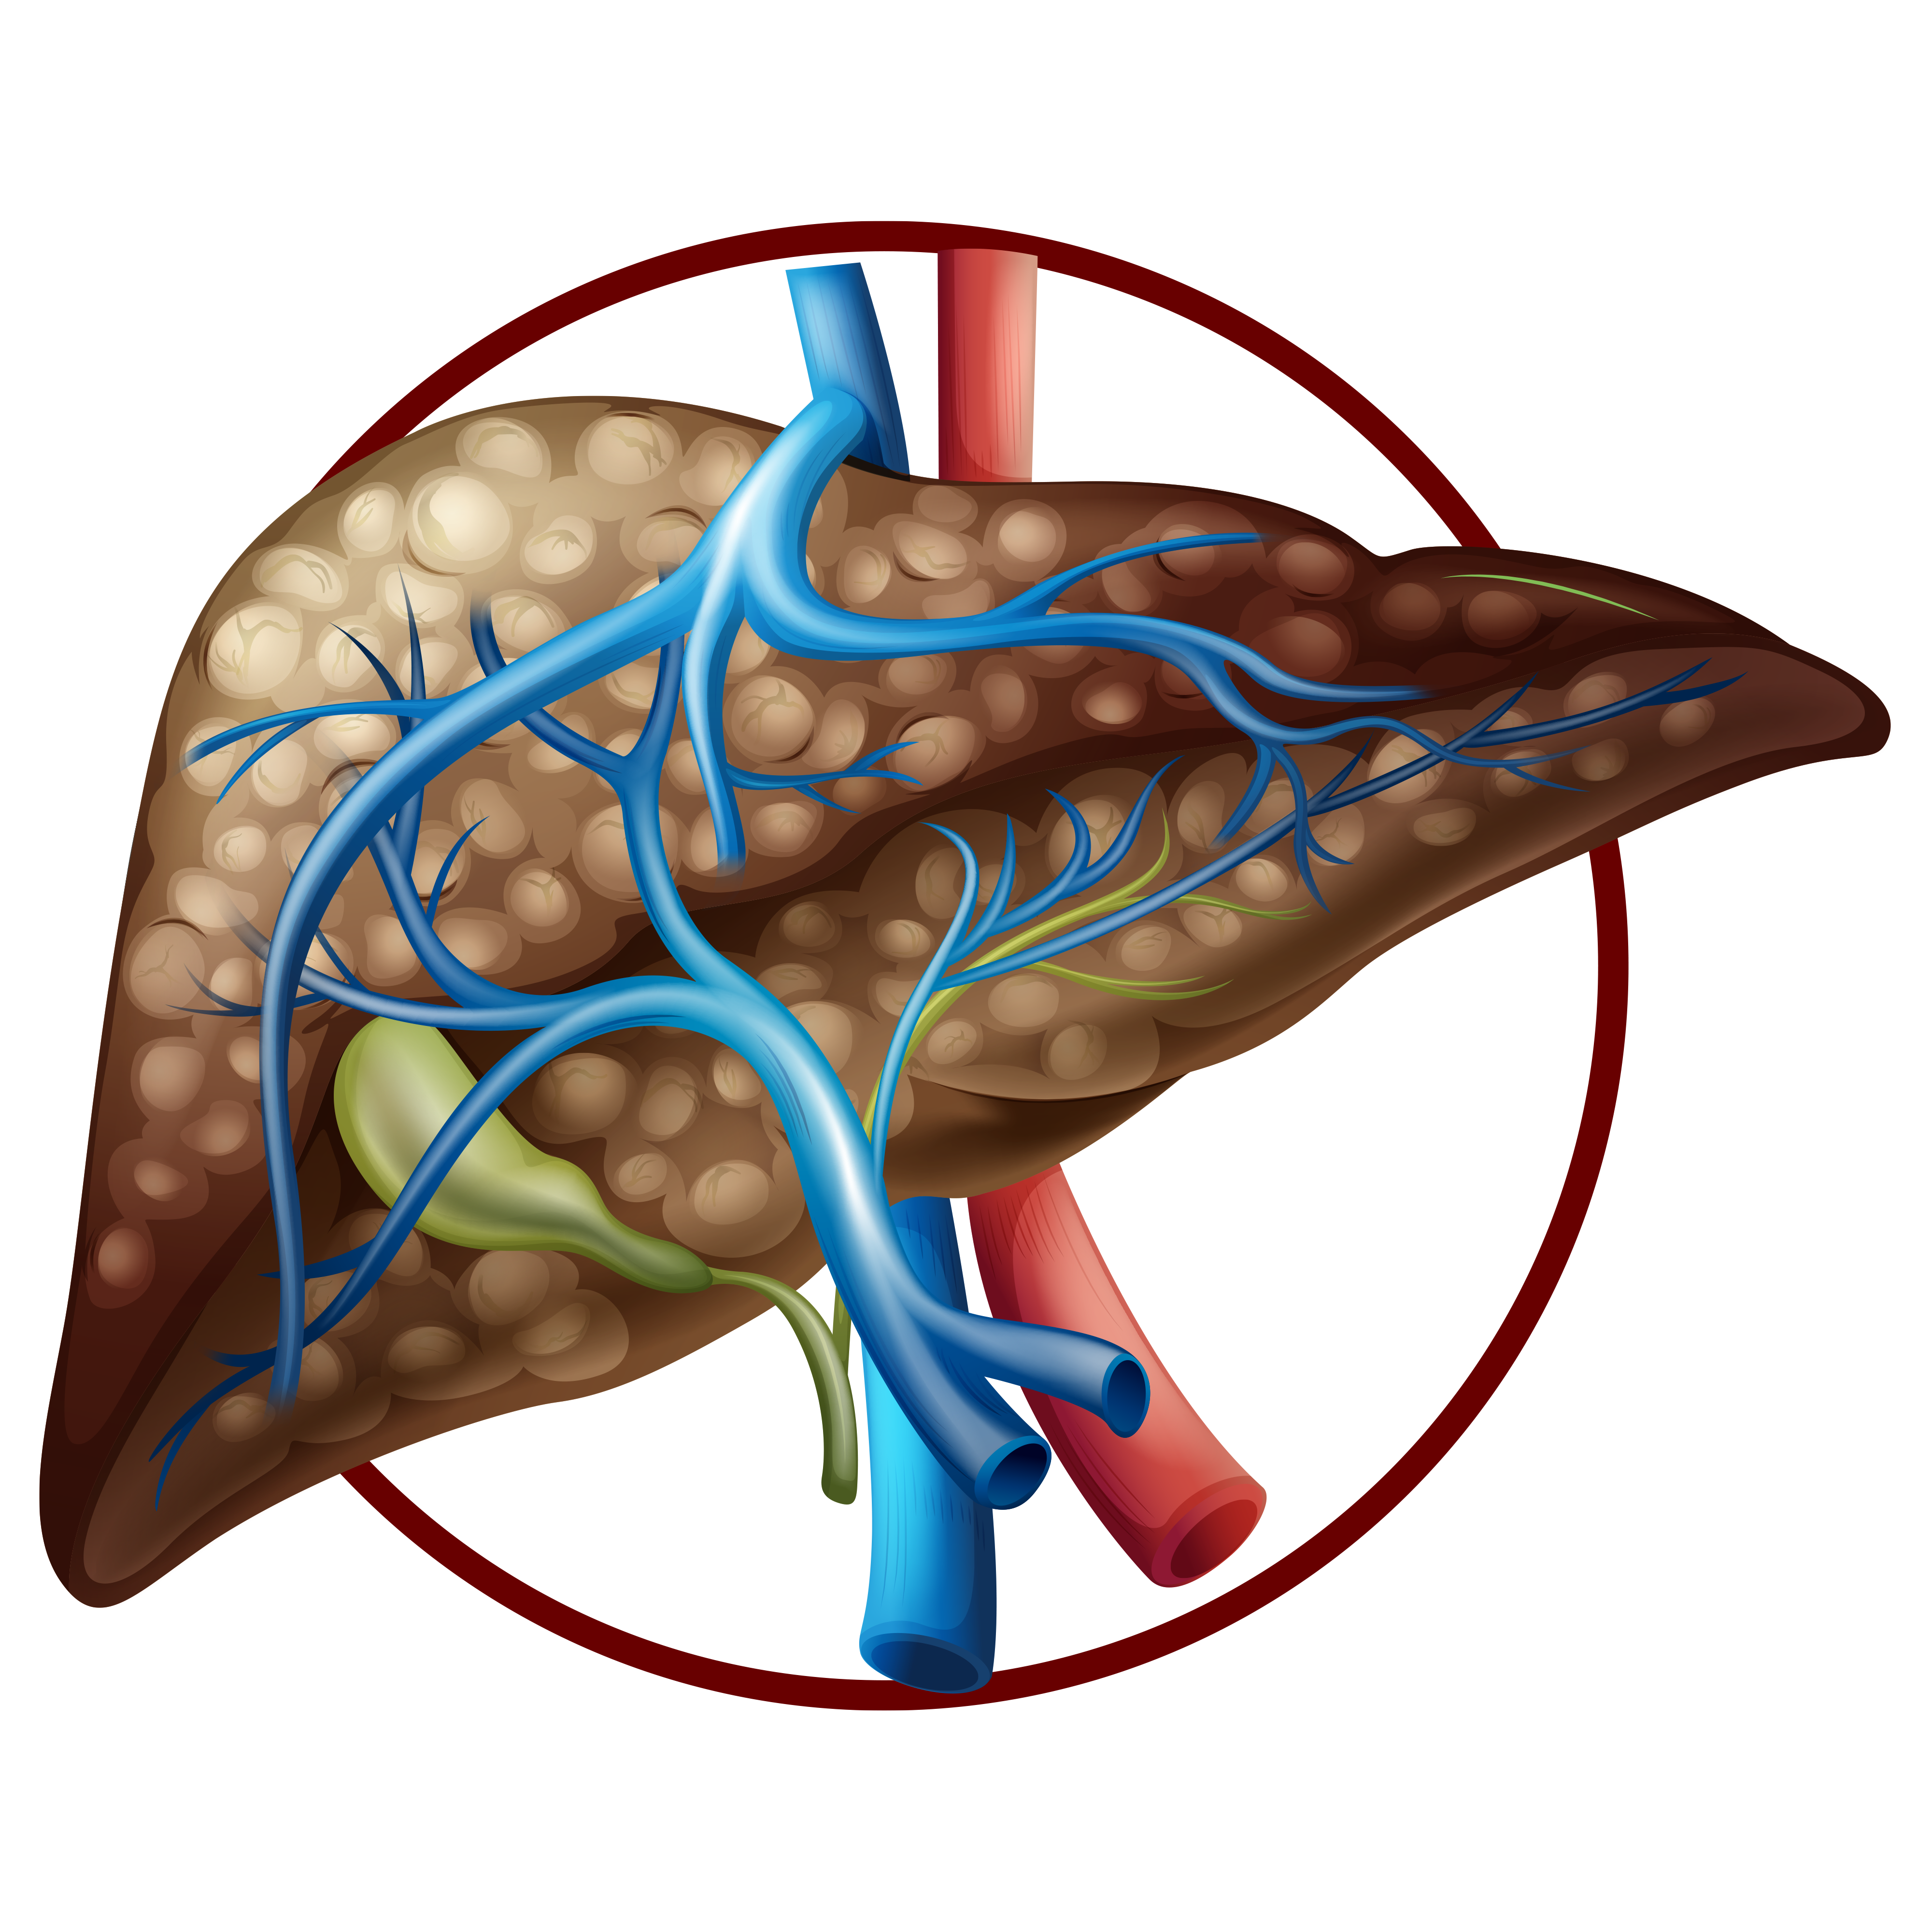

Progressive liver damage from alcohol or chronic illness.It leads to scarring, fluid buildup, and liver failure if unmanaged.